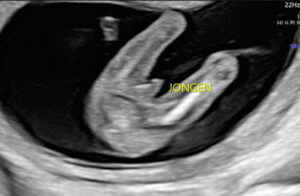

Geslachtsbepaling

- vanaf 14 weken

- 2D echo van 10-12 minuten

- 4 zwart-wit fotoprints

- Na afloop van de echo ontvang je een selectie van de mooiste beelden en clips via de e-mail